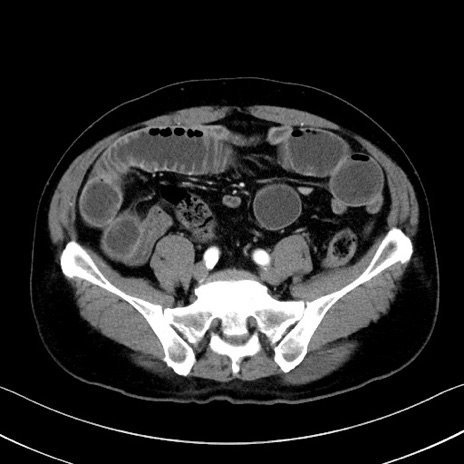

症例35(横断像)

【症例】70歳代 男性

【主訴】腹部膨満、嘔吐

【現病歴】昨日より腹部膨満感出現。本日増悪し、仙痛出現。嘔吐あり、受診。

【既往歴】糖尿病、胆摘後

【身体所見】BP 149/80mmHg、HR 74/min、BT 35.9℃、腹部:膨満、軟、圧痛なし。腸雑音減弱あり。上腹部正中切開瘢痕あり。

【データ】WBC 13500、CRP 1.72